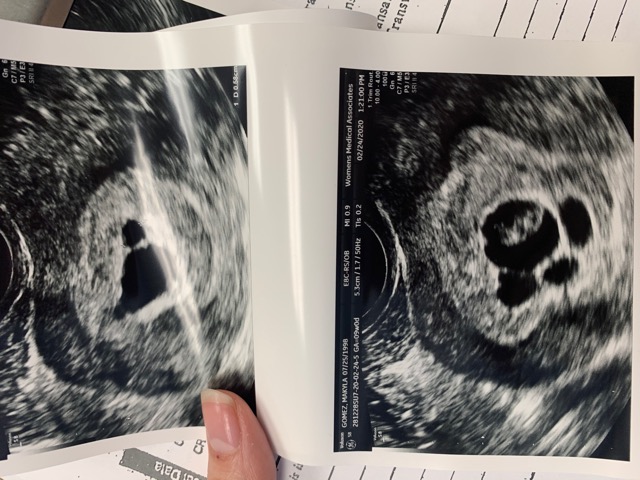

Partial Molar Pregnancy Diagnoses But Strong Heartbeat... - Glow Community

Partial molar pregnancy diagnoses but strong heartbeat... - Glow Community glowing.com

pregnancy molar partial diagnoses heartbeat strong but

Possible Partial Molar Pregnancy? | BabyCenter

Possible partial molar pregnancy? | BabyCenter community.babycenter.com

molar pregnancy partial possible babycenter

Partial Molar Pregnancy ? - Glow Community

Partial molar pregnancy ? - Glow Community glowing.com